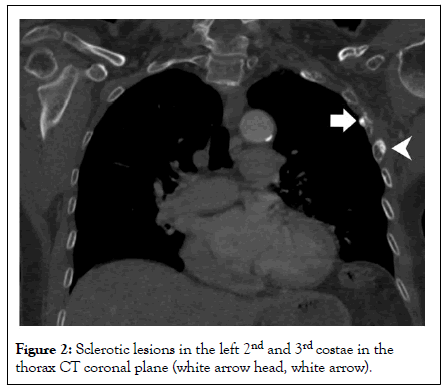

A 70-year-old female patient was diagnosed with left breast cancer in 2011 and no significant pathology was detected in the PET CT report taken after left mastectomy at that time. The patient was admitted to us with a new diagnosis of ovarian Ca. Thoracic CT scans performed for staging revealed sclerotic lytic bone lesions in the left 2nd, 3rd and 4th costae, which were not present before. Considering the absence of involvement in Pet CT in a patient with a history of RT and subcutaneous sequelae changes in the same region, sclerotic lesions in the costae were evaluated in favor of osteoradionecrosis and sclerotic bone metastasis was considered in the differential diagnosis with a lower probability (Figures 1 and 2). At the same time, there was a hyperdense, smoothly circumscribed, bone lesion in the left transverse process of the L1 vertebra (Figure 3). The lesion in the L1 vertebra was measured with a mean density of 1009 HU and was evaluated in favor of enostosis due to its characterization [5].

Figure 3: Bone islet in the L1 vertebra in the axial plane, bone window (black arrow in A) and density measurement (B).

Additionally, a well-circumscribed hyperdense lesion was noted in the left transverse process of the L1 vertebra. The lesion was approximately 1.2 cm in diameter, homogeneously dense and without surrounding bone destruction or cortical erosion. Measurement of Hounsfield Unit (HU) attenuation revealed an average density of 1009 HU-a level significantly higher than typical bone metastases. No perilesional sclerosis or reactive bone formation was noted. These features were characteristic of a benign enostosis [7].

Enostosis (bone island) is an incidental benign focus of compact bone that develops within cancellous regions, typically demonstrating extremely high attenuation values on CT-often exceeding 1000 HU. Common sites include the pelvis, femora, humeri, and vertebrae. Enostoses are round or ovoid, sharply marginated and lack bone destruction or reactive sclerosis. They do not enhance with contrast nor demonstrate metabolic activity on PET-CT scans, making them radiologically distinguishable from sclerotic metastases.

In this patient, the L1 vertebral lesion displayed the classic imaging features of enostosis, with no perilesional edema or contrast enhancement, reaffirming its benignity. Recognition of enostosis is essential in oncologic imaging, as misinterpreting it as a metastatic deposit could alter staging and lead to undue psychological and therapeutic consequences [9].